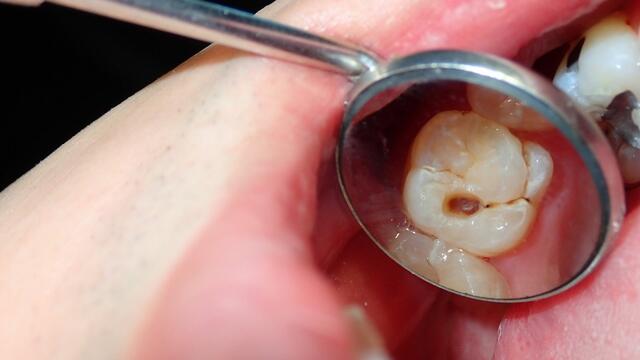

A fogszuvasodás ma is az egyik leggyakoribb fogászati probléma, amely kortól függetlenül sok embert érint. Bár a modern fogápolási eszközök és a fogászati kezelések folyamatosan fejlődnek, az életmód és a táplálkozási szokások miatt a fogak még mindig könnyen károsodhatnak. A fogromlás gyakran hosszú ideig észrevétlen marad, ezért sok esetben csak akkor derül ki a probléma, amikor már komolyabb beavatkozásra van szükség.

fogszuvasodás

A fogromlás egyik leggyakoribb oka a cukros ételek és italok rendszeres fogyasztása. A szájban lévő baktériumok a cukrot savvá alakítják, amely fokozatosan károsítja a fogzománcot. Ha ez a folyamat tartósan fennáll, a zománc elvékonyodik, majd kialakulhat a fogszuvasodás.

Különösen a szénsavas üdítők, energiaitalok, cukros kávék és édességek jelenthetnek kockázatot. A savas italok ráadásul közvetlenül is gyengíthetik a fogzománcot, így a fogak érzékenyebbé és sérülékenyebbé válhatnak.